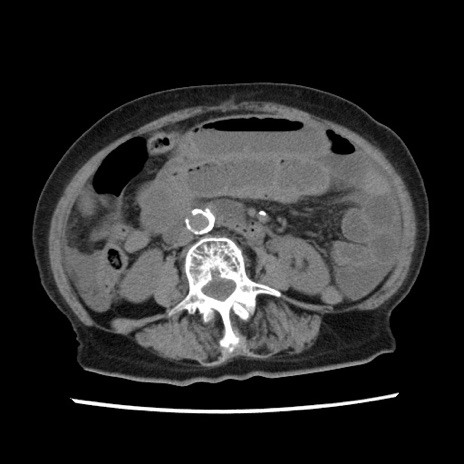

症例1(横断像)

【症例】80歳代女性

【主訴】腹痛

【現病歴】8時間前から腹痛あり来院。

【既往歴】糖尿病、脂質異常症、子宮体癌にて子宮全摘術

【身体所見】意識清明・会話良好だが腹痛で苦悶様、全腹部にわたって反跳痛と圧痛あり

【データ】WBC 13600、CRP 0.14、LDH 224、CK 90